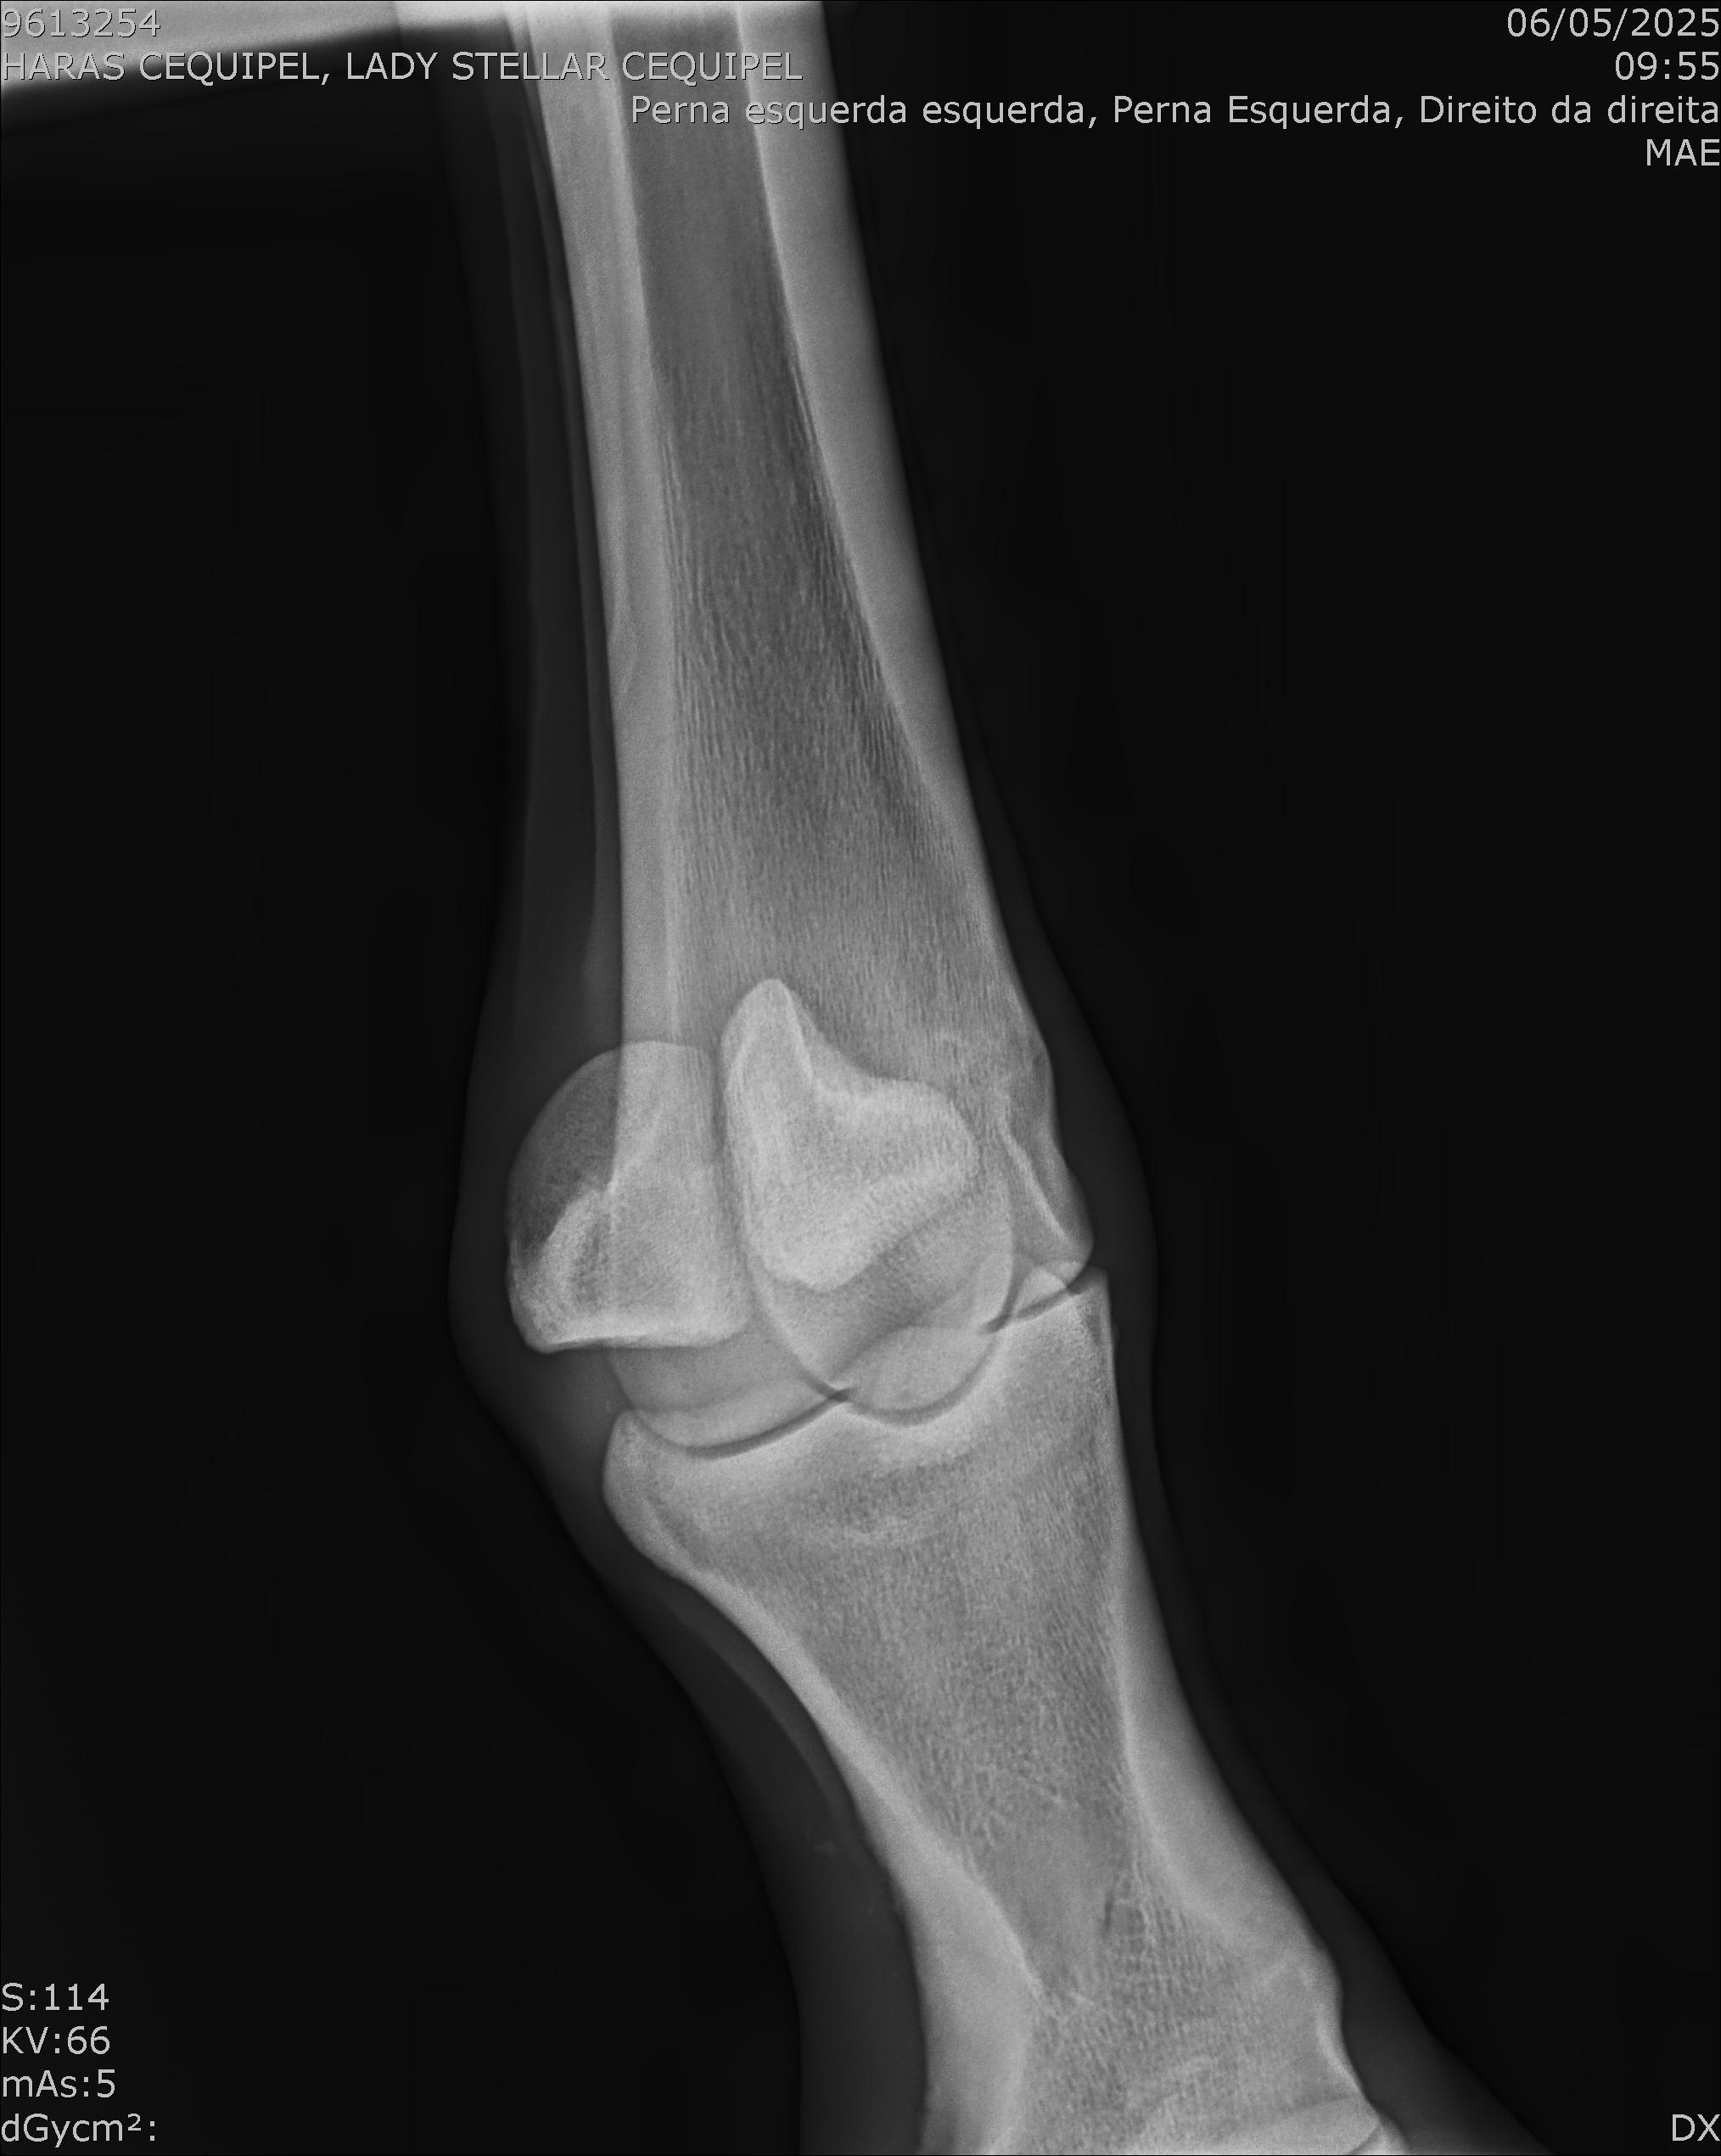

:: RAIOS-X DO LOTE